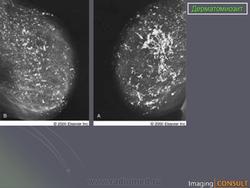

Изменения в легких, обусловленные самим заболеванием, относительно редки. К ним относят интерстициальный фиброз, иногда с развитием хронического легочного сердца. Аспирация слюны и пищи и гиповентиляция легких предрасполагают к развитию банальной инфекции.

3) висцерально-мышечный синдром: поражение дыхательных мышц, включая диафрагму (одышка, высокое стояние и вялость дыхательных экскурсий диафрагмы, снижение жизненной емкости легких); мышц глотки, пищевода, гортани (дисфагия с поперхиванием, дисфония), миокарда (миокардит, дистрофия, интерстициальный отек);

Британский журнал радиологии (2005)

http://radiographics.rsna.org/content/31/6/1651.full